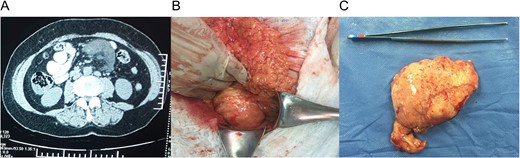

(A) Computed tomography (CT) with a 9 × 7 × 4 cm mass within the small bowel mesentery near the root of the mesentery. (B) Mass in the root of small bowel mesentery near the mesenteric vessels. (C) External surface of the mass.

The external surface of the mass had a yellowish like-fat aspect and contained white milky fluid, the mass contained some cystic lesions and the wall was 0.5 cm in width (Fig. 1C). Pathology reported encapsulated fat tissue surrounded by dilated lymph vessels that contained lymphocytes. Immunohistochemical study for D2-40 was positive. Lymphangioma cavernous was the final diagnostic (Fig. 2A–C).